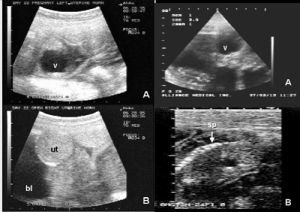

醫學超音波檢查的工作原理與聲納有一定的相似性,即將超音波發射到人體內,當它在體內遇到界面時會發生反射及折射,並且在人體組織中可能被吸收而衰減。因為人體各種組織的形態與結構是不相同的,因此其反射與折射以及吸收超音波的程度也就不同,醫生們正是通過儀器所反映出的波型、曲線,或影象的特徵來辨別它們。此外再結合解剖學知識、正常與病理的改變,便可診斷所檢查的器官是否有病。

目前,醫生們套用的超聲診斷方法有不同的形式,可分為A型、B型、M型及D型四大類。

A型:是以波形來顯示組織特徵的方法,主要用於測量器官的徑線,以判定其大小。可用來鑑別病變組織的一些物理特性,如實質性、液體或是氣體是否存在等。

B型:用平面圖形的形式來顯示被探查組織的具體情況。檢查時,首先將人體界面的反射信號轉變為強弱不同的光點,這些光點可通過螢光屏顯現出來,這種方法直觀性好,重複性強,可供前後對比,所以廣泛用於婦產科、泌尿、消化及心血管等系統疾病的診斷。

M型:是用於觀察活動界面時間變化的一種方法。最適用於檢查心臟的活動情況,其曲線的動態改變稱為超聲心動圖,可以用來觀察心臟各層結構的位置、活動狀態、結構的狀況等,多用於輔助心臟及大血管疫病的診斷。

D型:是專門用來檢測血液流動和器官活動的一種超聲診斷方法,又稱為都卜勒超聲診斷法。可確定血管是否通暢、管腔有否狹窄、閉塞以及病變部位。新一代的D型超音波還能定量地測定管腔內血液的流量。近幾年來科學家又發展了彩色編碼都卜勒系統,可在超聲心動圖解剖標誌的指示下,以不同顏色顯示血流的方向,色澤的深淺代表血流的流速。現在還有立體超聲顯象、超聲CT、超聲內窺鏡等超聲技術不斷湧現出來,並且還可以與其他檢查儀器結合使用,使疾病的診斷準確率大大提高。超音波技術正在醫學界發揮著巨大的作用,隨著科學的進步,它將更加完善,將更好地造福於人類。